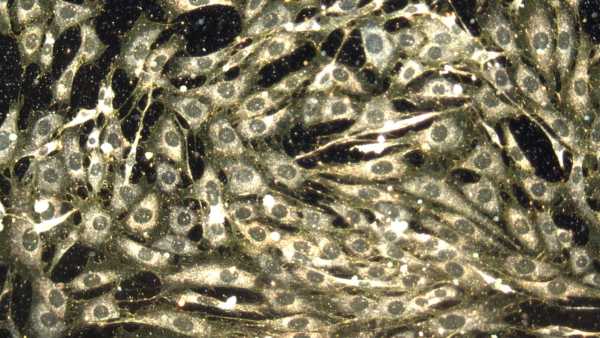

Нове дослідження показує, що тепер можливо розводити мишей із повністю розвиненою та функціональною імунною системою людини. (Зображення: Evgenyi_Eg via Getty Images)